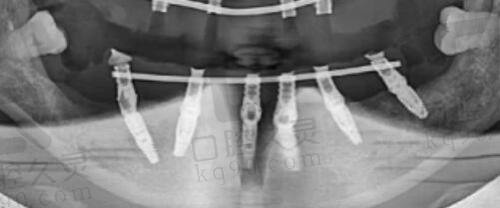

在碧莲盛,植发手术的价格是按照毛囊单位来算的。啥是毛囊呢?它就像是头发生长的“种子”,每个毛囊可能会长出一根或者好几根头发。所以啊,毛囊单位的数量直接就决定了植发手术的复杂程度和费用。碧莲盛提供了好多种不同毛囊单位的植发套餐,能满足不同患者的需求。从1500毛囊单位到2500毛囊单位,甚至还有更高的套餐,价格都标得清清楚楚,让你选的时候心里有谱。

要是你脱发情况比较轻,只需要局部改善一下,那1500毛囊单位的植发套餐就挺合适。这个套餐可以用来调整发际线、加密头顶,或者修复小面积的脱发。在碧莲盛,1500毛囊单位的植发手术价格一般比较实惠,特别多第一次尝试植发手术的患者都选这个。不过具体价格会因为个人情况、手术难度,还有医生经验这些因素有点差别,但总体来说,性价比是真的高。

要是你的脱发情况比较重度,需要大面积改善,那2500毛囊单位的植发套餐可能更适合你。这个套餐能更有效地增加头发密度,让你的头看起来更饱满。在碧莲盛,2500毛囊单位的植发手术价格适中,既能确保手术成效,又不会让患者有太大的经济压力。当然,具体价格还得根据个人情况来定,但碧莲盛的价格体系特别透明合理。

要是你脱发面积比较大,需要全方面改善,3000毛囊单位的植发套餐就是个不错的选择。这个套餐能更全方面地覆盖脱发区域,让头发看起来更浓密自然。在碧莲盛,3000毛囊单位的植发手术价格相对高一些,但想想手术成效和长期好处,这笔钱花得还是值得的。碧莲盛的专精医生会根据患者的具体情况制定个性化的手术方案,确保手术成效达到至佳。

要是你脱发情况特别重度,需要大面积植发,4800或者5000毛囊单位的植发套餐可能就是更好的选择了。这些套餐能较大程度地增加头发密度,让你的头看起来更饱满健康。当然,毛囊单位数量越多,手术价格也就越高。不过在碧莲盛,你不用担心价格不透明或者有隐形消费。碧莲盛一直坚持诚信经营,所有价格都公开透明,让你选得放心。